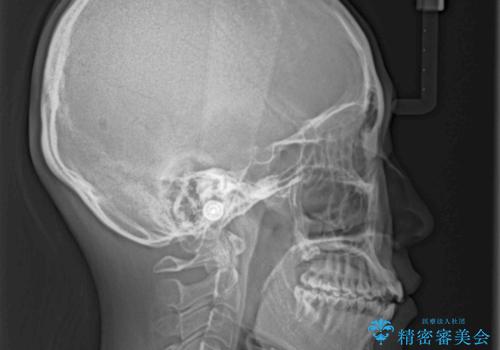

開咬の治療は、前歯を閉じるように動かすとともに、上下臼歯を圧下(骨内にめり込ませる)させることで進めて行きます。

インビザラインは臼歯の圧下を効果的に行えるため、インビザラインを用いて矯正治療を行うこととしました。